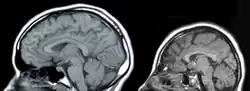

![]() dziecko z mikrocefalią (po lewej) w porównaniu do dziecka z prawidłową wielkością głowy | |

Mikrocefalia (małogłowie, łac. microcephalia, ang. microcephaly) – wada rozwojowa charakteryzująca się nienaturalnie małymi wymiarami czaszki (a więc również puszki mózgowej). Małogłowie rozpoznaje się gdy obwód głowy, mierzony pomiędzy okolicą tuż nad wałami nadoczodołowymi do najbardziej ku tyłowi wysuniętej części kości potylicznej (opisthocranion), nie przekracza wartości średniej dla płci i wieku w danej populacji pomniejszonej o 3 odchylenia standardowe (SD). Mikrocefale mają masę mózgu mniejszą niż 900 g. Mikrocefalia może wystąpić jako wada izolowana lub element zespołu wad.